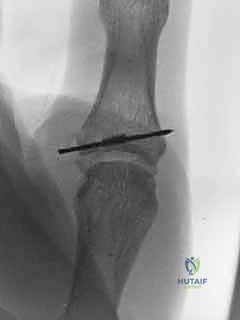

3. التصوير الإشعاعي (Imaging)

لا يكتفي الأستاذ الدكتور هطيف بالفحص السريري، بل يعتمد على التصوير لتأكيد التشخيص واستبعاد الإصابات المصاحبة:

* الأشعة السينية (X-rays): تُجرى دائماً قبل اختبار الإجهاد لاستبعاد وجود كسور (مثل الكسر القلعي - Avulsion fracture، حيث ينفصل جزء صغير من العظم مع الرباط الممزق).